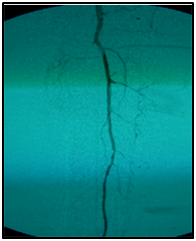

An example: A 77-year-old, diabetic woman, complaining of rest pain in her left leg and carrier ulceration on the left hallux. The physical examination showed absence of distal pulses in her left leg. Color Doppler ultrasound performed before treatment confirmed BTK critical lesions with no patency and a diagnosis of CLI.

Endovascular procedure was done with antegrade access in the ipsilateral common femoral artery, diagnostic angiography confirmed: Patency of the femoral-popliteal axis, occlusion of the posterior and anterior tibial arteries, two critical stenotic lesions in the fibular artery and revascularization of the dorsalis pedis and plantar arteries by the fibular artery. To treat the fibular critical atherosclerotic lesions were performed a percutaneous transluminal angioplasty using a 0.0018in.guidewire, catheter support and a catheter balloon (3,0x6 mm and 3,5x 15mm).

Final angiographic control showed patency of the fibular artery and dorsalis pedis, with direct flow for the first metatarsal artery, thus guaranteeing enough flow to heal the ulcer in six months after the procedure. In conclusion endovascular treatment has a high technical eligibility with good reported outcomes and represents an alternative for diabetics with CLI Disease (Figure 1 and 2).

• Figure 1 Angiography from left to right showing femoral-popliteal axis, occlusion of the posterior and anterior tibial arteries, in detail two critical stenotic lesions in the fibular artery.